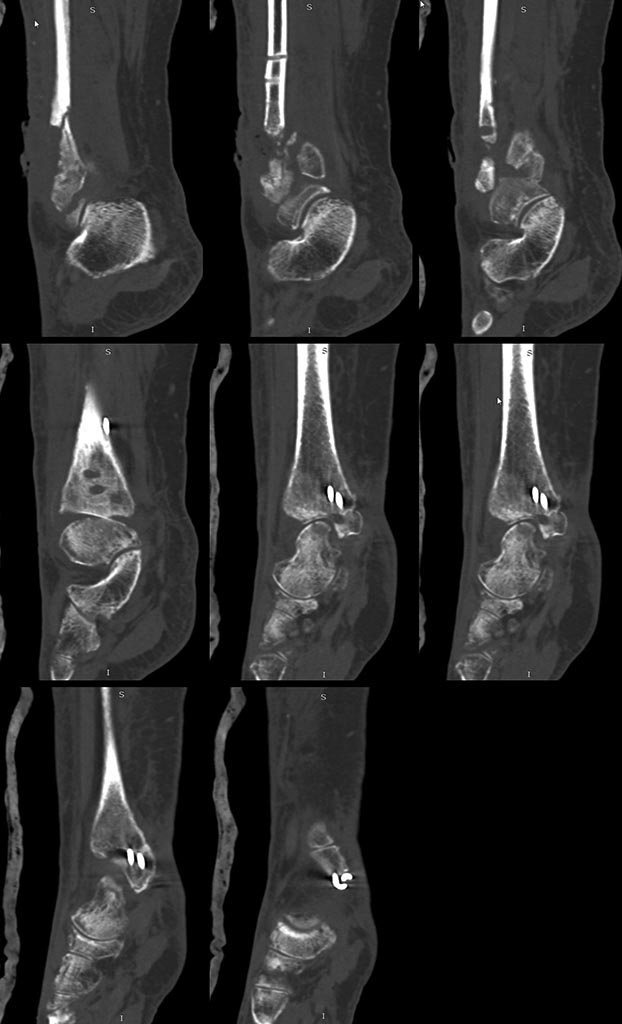

КТ

ИМХО: Сделайте фистулографию, вовлечен ли голеностопный сустав (на предоставленном фото трудно определить)? Не исключено, что инфекция может располагаться также в большеберцовой кости (позиционные винты). По данным обследования повторная санация:

-остеонекрэктомия м/б кости (не исключена резекция места несращения) а также б/б кости (с удалением МК);

-при вовлечении г/ст (большая вероятность) - дополнить артротомией с артродезом в АВФ;

-при интактном г/ст суставе, заполнение костных полостей после некрэктомии (одно-или -двухэтапно) при стабильности - не исключена гипсовая лонгета.